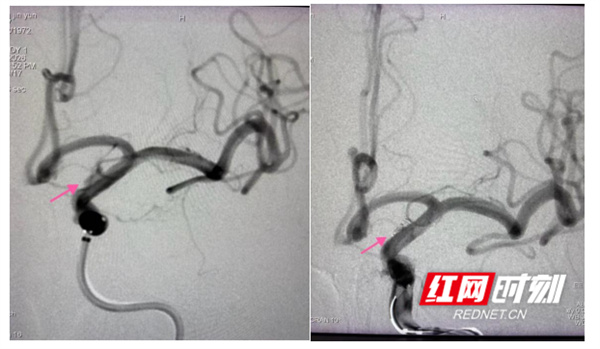

血泡样动脉瘤栓塞前后对比。

面对高风险挑战,脑病科介入团队沉着应对,术前反复推演手术路径、制定个体化“支架辅助弹簧圈栓塞”方案;术中精准操控微导管,在瘤体内精细填塞弹簧圈并植入支架重塑载瘤动脉。术后造影显示,动脉瘤完全闭塞、载瘤动脉血流通畅,患者术后恢复良好,已脱离生命危险。其余3例常规动脉瘤患者,均通过微创股动脉穿刺完成栓塞,无需开颅、创伤极小,大幅缩短住院周期。